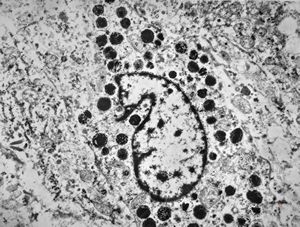

F,69y. | cystadenoma (Warthin tumor) … caruncula - (modified mitochondria in an autolysed sample)